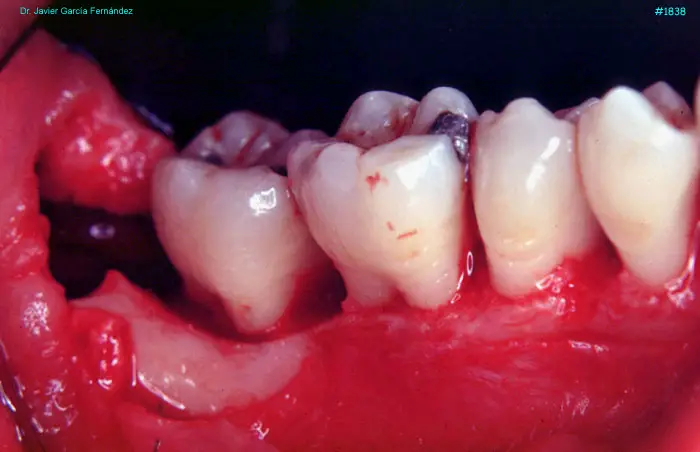

image 104